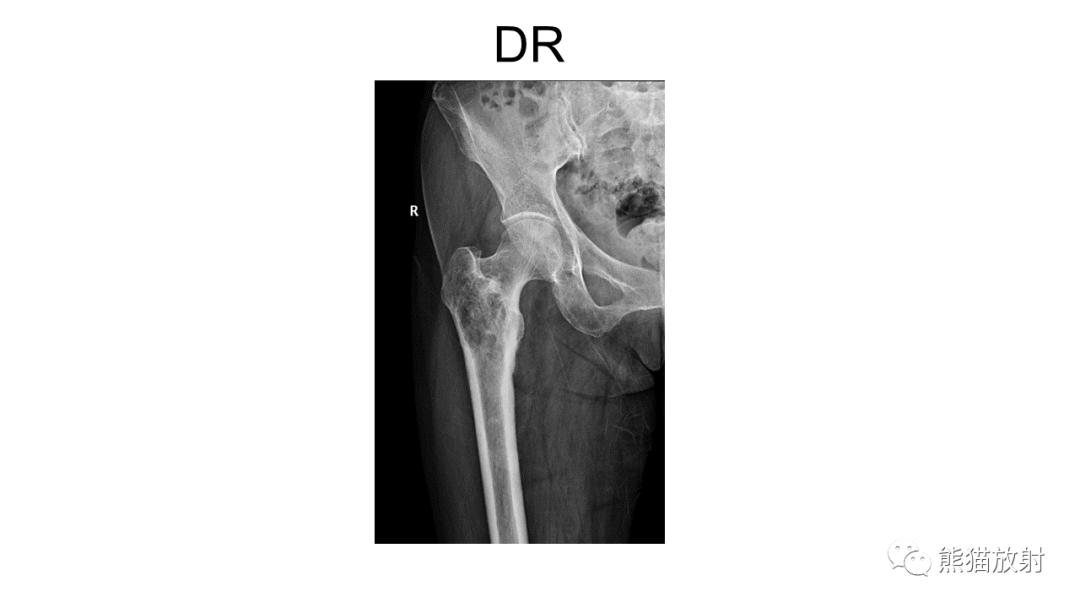

【病例】软骨肉瘤I级 VS 去分化软骨肉瘤-1